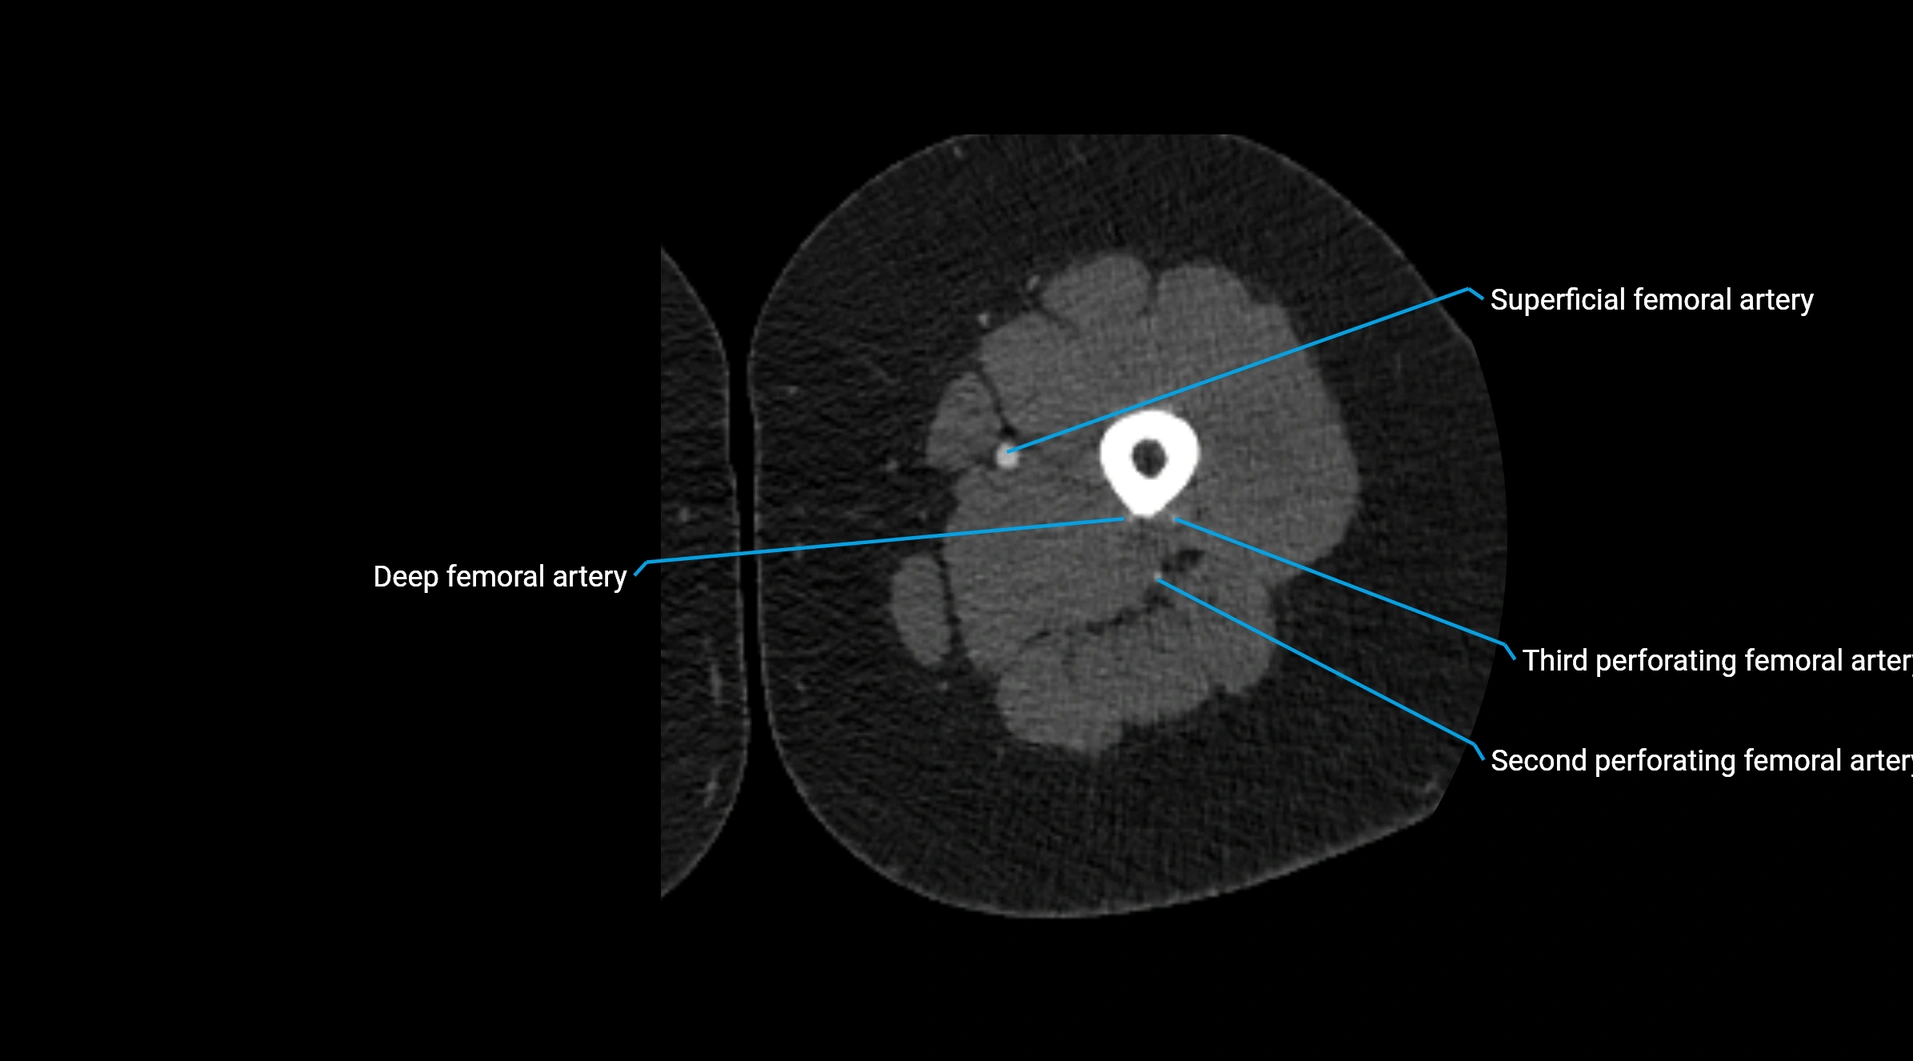

CT images

image

Contrast-enhanced CT (CTA):

• Gold standard for abdominal aortic imaging

• Provides excellent detail of lumen, wall, aneurysm, thrombus, and branch vessels

• Multiplanar and 3D reconstructions help in aneurysm measurement, stent graft planning, and dissection evaluation